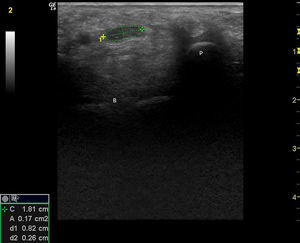

Observación clínicaMujer de 84 años, hipertensa controlada, presentaba desde hace 2 meses lesiones cutáneas en ambas manos de tipo vasculítico asociadas a cianosis del 1.er, 2.° y 3.° dedos, y a dolor intenso que motivaron hospitalización en urgencia por sospecha de vasculitis sistémica. En la anamnesis dirigida, no había elementos de conectivopatía ni consumo de drogas. Recibía enalapril para tratar su hipertensión arterial. En el examen físico destacaban lesiones periungueales, en pulpejos, indicativas de vasculitis, pero llamaba la atención su distribución dermatómica, la severa hipoestesia asociada en el mismo territorio y la importante atrofia de la eminencia tenar, de manera bilateral (fig. 1). El resto del examen era normal; en particular, no había lesiones cutáneas en otras localizaciones y su tensión arterial era normal. Se realizó estudio: hemograma y velocidad eritrocitaria de sedimentación normales, función renal y orina completa normales, factor reumatoideo negativo, anticuerpos antinucleares negativos, perfil ENA detallado negativo, ANCA c y p negativos. La paciente refería de alteraciones de la sensibilidad con parestesias nocturnas y falta de fuerza en manos con tiempo de evolución prolongado, por lo que ya había consultado. Se había hecho el diagnóstico de STC, realizándose una electromiografía de extremidades superiores un año antes. Esta mostraba ya un severo atrapamiento de ambos nervios medianos a nivel de los túneles carpianos, con denervación completa de las eminencias tenares. Se realizó estudio ultrasonográfico de la paciente evidenciando a la entrada del túnel a nivel del pisiforme, un nervio mediano derecho de 17mm2 de área (normal=± 10mm2)1,2 (fig. 2), con presencia central de una arteria mediana remanente (fig. 3). El nervio mediano izquierdo estaba también engrosado, con un área nivel del pisiforme de 18mm2. Ambos nervios aparecían atrapados en el túnel carpiano en los cortes longitudinales (fig. 4).

Corte transversal del nervio mediano derecho a nivel de la entrada del túnel del carpo, con medición del área del nervio con elipse (0,17cm2), a nivel del pisiforme P (B: hueso grande). (Imagen obtenida con ecógrafo General Electrics LOGIC e, con un transductor linear de 8-12 mHz usando para esta imagen una frecuencia de 12 mHz y un agrandamiento máximo).